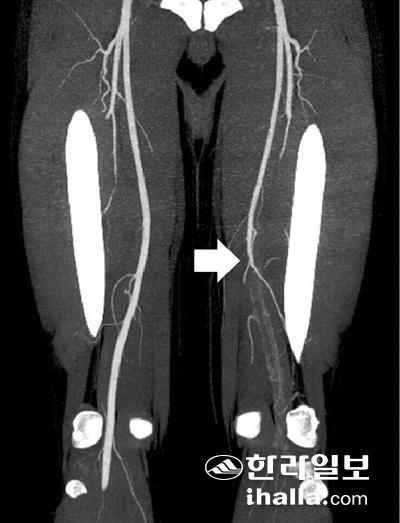

혈관조영술에서 혈관이 막힌 사진.